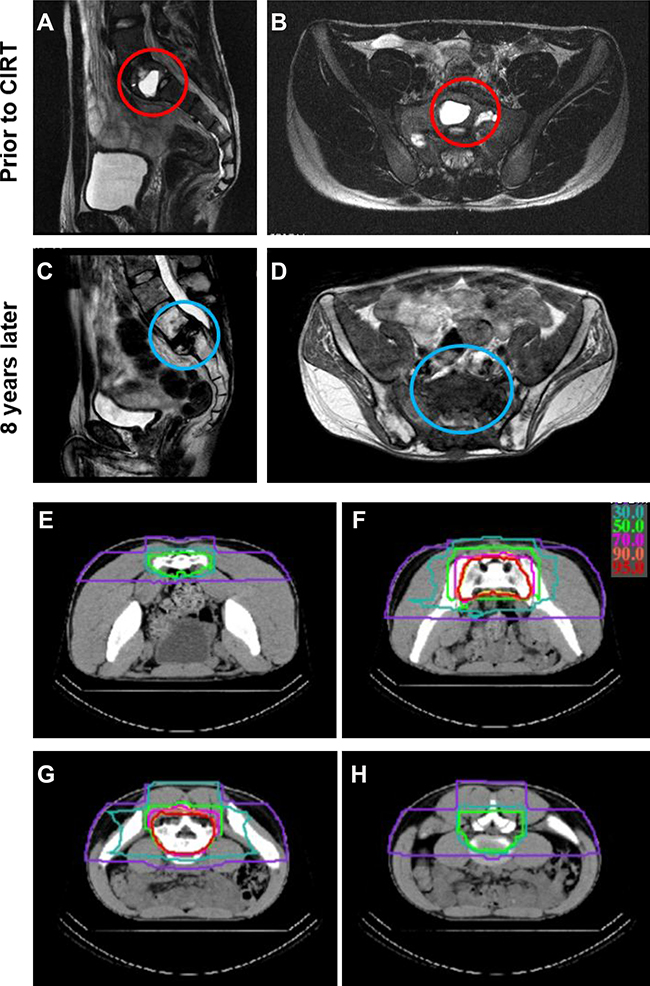

Table 2 summarizes the characteristics of CIRT treatments. Twenty-four patients were irradiated to their pelvis (12 sacral, 11 iliac, and 1 pubic). The remaining two patients received CIRT to the mediastinum and chest wall paravertebral area, respectively. The median irradiation volume was 452 cm3 (172–1774 cm3). The majority of patients received 70.4 (18 patients) or 73.6 (3 patients) Gy RBE in 16 fractions. Figure 1 shows an example of a patient with sacral (S1) osteosarcoma with pre- and post-CIRT magnetic resonance imaging (a-d) and the CIRT treatment plan (e-h).

Figure 1: An example of a treated case with unresectable sacral (S1) osteosarcoma. (A–B) show magnetic resonance imaging (MRI) scans prior to carbon ion radiotherapy (CIRT) in the sagittal (A) and horizontal (B) planes with the tumor highlighted in the red circles. (C–D) show MRI scans 8 years after CIRT in the sagittal (C) and horizontal (D) planes without any tumor recurrence (blue circles) but with obvious fracture in S1. (E–H) show selected computed tomography (CT) cross sectional views of the CIRT dose distribution (isodose lines: red 95%, orange 90%, pink 70%, light green 50%, green 30%, purple 10%).